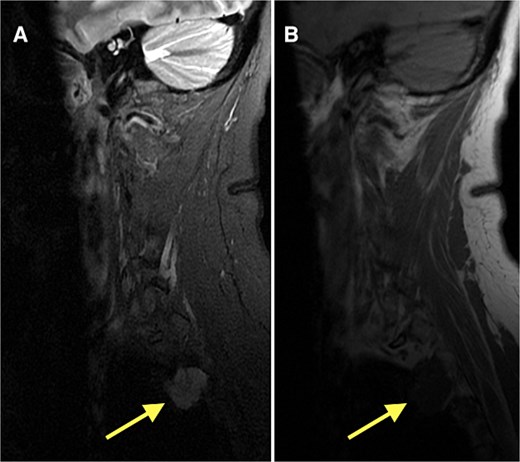

Following diagnosis, the patient was referred to orthopedic oncology and underwent serial multiplanar MRI of the entire spine, as well as CT of the chest. Imaging revealed a lobulated T1-hypointense, T2-hyperintense lesion at the lateral margin of the right T2–T3 neural foramen measuring 2.3 cm (anteroposterior) × 2.2 cm (Fig. 3). Given concern for a potential primary lesion, this mass was subsequently biopsied. The patient continues to follow closely with the oncology service for further evaluation, surveillance, and management.

MRI of the thoracic spine demonstrating a lobulated T1-hypointense (B), T2-hyperintense lesion (A) at the lateral margin of the right T2–T3 neural foramen, measuring 2.3 × 2.2 cm (anteroposterior × transverse).